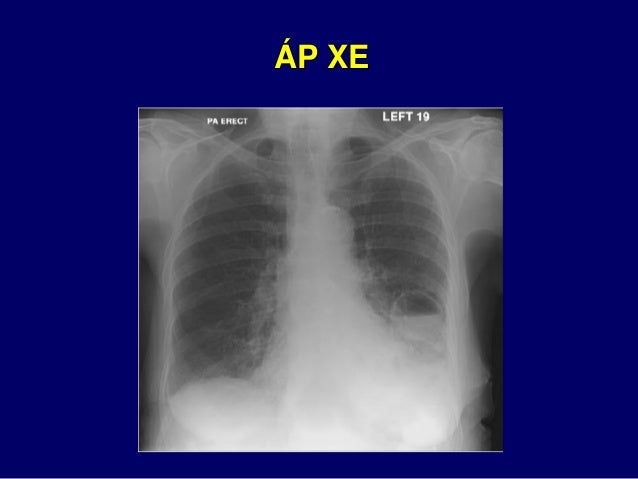

5. 5. PHIM XQ PHỔI ĐẠT CHUẨN  Hít đủ sâu  Tư thế chụp: đứng ngay thẳng  Tia sau trước  Cường độ tia đúng mức

6. 6. Hít không đủ sâu  Mờ vùng đáy giả tạo Hít lại cho đủ sâu  Biến mất vùng mờ ở đáy

7. 7. Cung sườn 9 sau Cung sườn 6 trước Nằm trên cơ hoành 1 2 3 4 5 6 7 8 9 1 2 3 4 5 6

8. 8. Tư thế chụp nằm Tư thế chụp đứng TƯ THẾ CHỤP ĐỨNG

9. 9. Tư thế chụp đỉnh ưỡn Hình ảnh tim giả lớn Tư thế chụp thẳng sau – trước Hình ảnh tim bình thường TƯ THẾ CHỤP ĐỨNG

10. 10. D1 D2 D1 D2 Bóng tim lớn hơn khi tia sau trước

11. 11. TƯ THẾ ĐỨNG NGAY